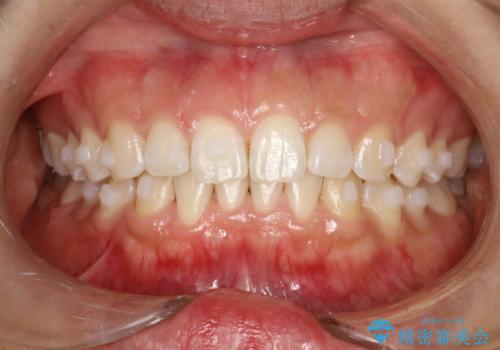

インビザライン中に歯の着色落としクリーニング PMTC

- インビザライン治療中に着色が気になるとのことでクリーニングを希望されました。PMTC30分コースを行いました。

インビザライン治療中には、歯の表面にアタッチメント(効率的に歯の移動をするもの)を設定します。そのため歯ブラシでは届きにくい細かい部分などに、歯石や着色がついてしまうことがあります。着色などを放置していると、着色なのか、虫歯なのかの判別もしずらく正確にお口の中の状態を診断できません。

矯正治療中も定期的に歯科医院にてPMTCを受けて、お口のケアを行うことをおすすめします。